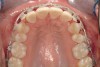

Figure 2a  Corticotomy SFOT. The patient presented with unesthetic anterior bridgework that was placed at age 14 to compensate for congenitally missing Nos. 7 and 10.

Figure 2a

Figure 2b  A corticotomy in SFOT is a surgical technique in which only the cortical bone is cut, perforated, or mechanically altered to the depth of the medullary bone and the medullary bone remains intact.

Figure 2b

Figure 2c  One week postsurgery with mesial buildups on Nos. 5 and 12 and thin pontics on archwire to conceal spaces during closure.

Figure 2c

Figure 2d  Prerestorative orthodontics was completed in 5 months. Final result 3 years, 4 months after completion.

Figure 2d

Figure 2e  Teeth Nos. 5 and 12 were converted to Nos. 6 and 11, and Nos. 6 and 11 were converted to Nos. 7 and 10. Nos. 4 and 13 were enlarged. Note stability and absence of orthodontic relapse. Before-and-after smiles.

Figure 2e

Figure 2f  Teeth Nos. 5 and 12 were converted to Nos. 6 and 11, and Nos. 6 and 11 were converted to Nos. 7 and 10. Nos. 4 and 13 were enlarged. Note stability and absence of orthodontic relapse. Before-and-after smiles.

Figure 2f

Figure 2g  Periodontist: Edward P. Allen, DDS, PhD. Prosthodontist: Robert R. Winter, DDS.

Figure 2g

Figure 2h  Periodontist: Edward P. Allen, DDS, PhD. Prosthodontist: Robert R. Winter, DDS.

Figure 2h